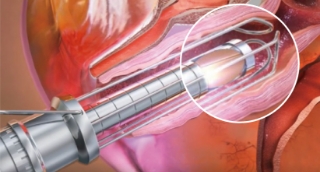

Vaginal handpiece

Reflection Mirror (90°, 360°)

Gold Coated Mirror (90° Reflection)

delivers focused heat with strong energy

Handpiece Guide

It makes the same distance between tissue with laser so it guaranty the uniform laser irradiation into tissue to guaranty overall good vaginal tightening result.